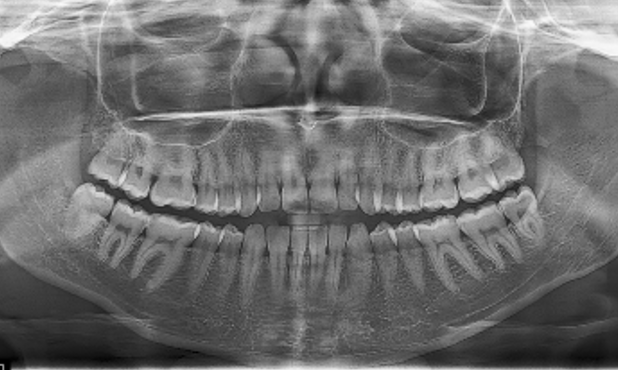

A 22-year-old female patient presented with a Class III malocclusion. She does not like her own profile. Her facial profile was straight with a slightly retrusive maxilla, the upper incisors were within normal inclination, and the lower incisors were retroclined. Bolton discrepency is on mandible for 6 teeth. A retruded upper lip and a normally positioned lower lip were noted. There was also a marked lack of midface support, and the constricted dental arches resulted in a narrow smile and pronounced dark buccal corridors.

Gaining overjet: Use forward-activating archwires to advance the proclined upper incisors and establish an adequate overjet.

Compensating proclination: Place retrocline brackets on UL2, UL1, UR1, and UR2 to counterbalance the created proclination.

Managing Bolton excess: Address the mandibular Bolton excess by increasing the mesiodistal expression on the upper canines, selecting procline brackets for UL3 and UR3.

Lower anterior control: To compensate for potential retroclination of the lower incisors during consolidation, use procline brackets on L3, L2, and L1 bilaterally.